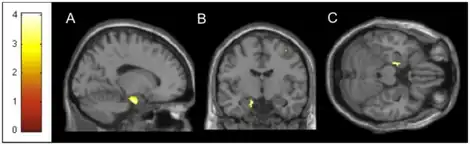

Despite MdDS causing significant disability, therapy for persistent MdDS remains virtually nonexistent. A pilot study has commenced utilizing repetitive transcranial magnetic stimulation (rTMS) this being a method of neuromodulation in which a local magnetic field is applied over the scalp to induce an electric current in the cortical structures underlying the coil. Low-frequency rTMS (e1 Hz) induces local inhibition, whereas high frequency rTMS (Q5 Hz) induces local excitation. The TMS studies have proved to help in lowering the symptoms of MdDS if the treatment is ongoing; however, it is not a cure.